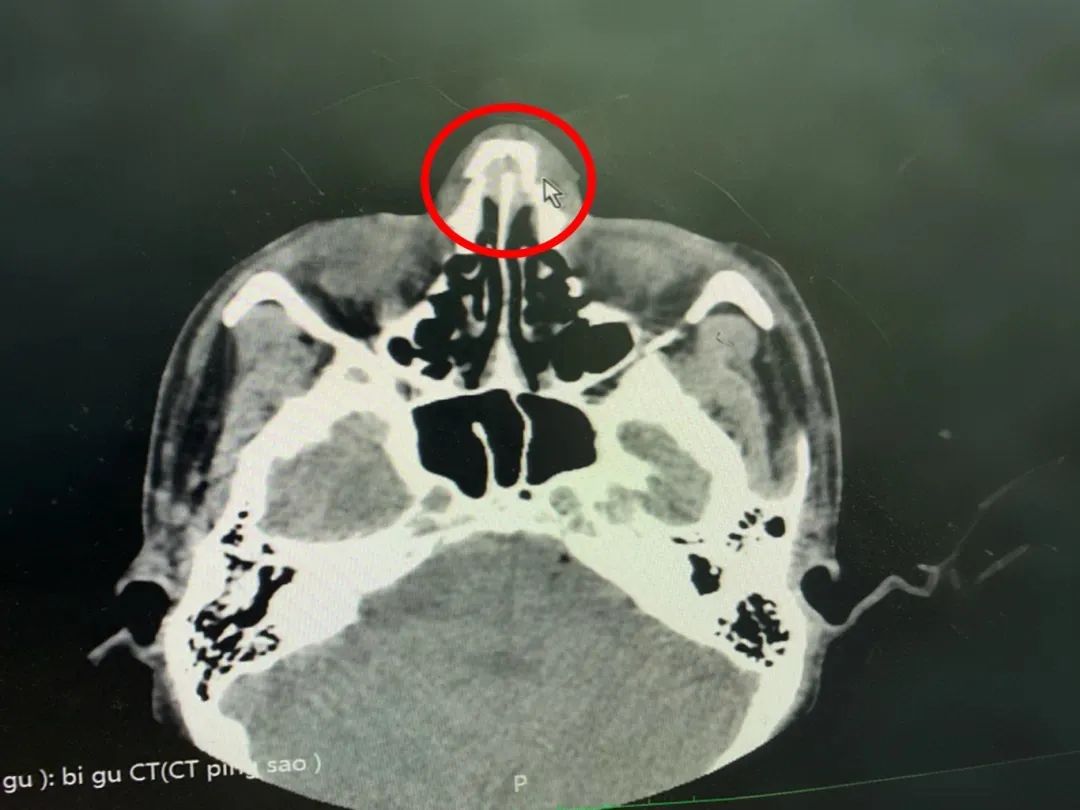

医生通过CT检查显示:双侧鼻骨骨折,断端错位,周围软组织稍肿胀,正如医生猜测的那样,确诊:“鼻骨骨折”。

据成都仁品耳鼻喉专科医院二病区副主任赵敏副主任医师介绍:“外鼻骨架由一对较薄的鼻骨及部分上颌骨额突构成,突出于面部,容易遭受外界暴力或机械性的创伤而发生鼻骨骨折。”

临床上,鼻骨骨折后最常见的症状是局部疼痛伴鼻腔出血,鼻部形态变化,鼻中隔骨折可能导致单侧或双侧鼻塞,严重的鼻骨骨折可能出现外鼻歪斜、肿胀、瘀血等。有报道显示,鼻骨骨折约占所有面部骨折的58%,不仅会影响面容,而且还会造成堵塞鼻孔等鼻腔生理性问题,严重者可同时致鼻窦、眼眶、颅底发生骨折及颌面部复合型骨折、意识丧失等,因此,临床上建议鼻骨骨折患者展开积极的治疗。